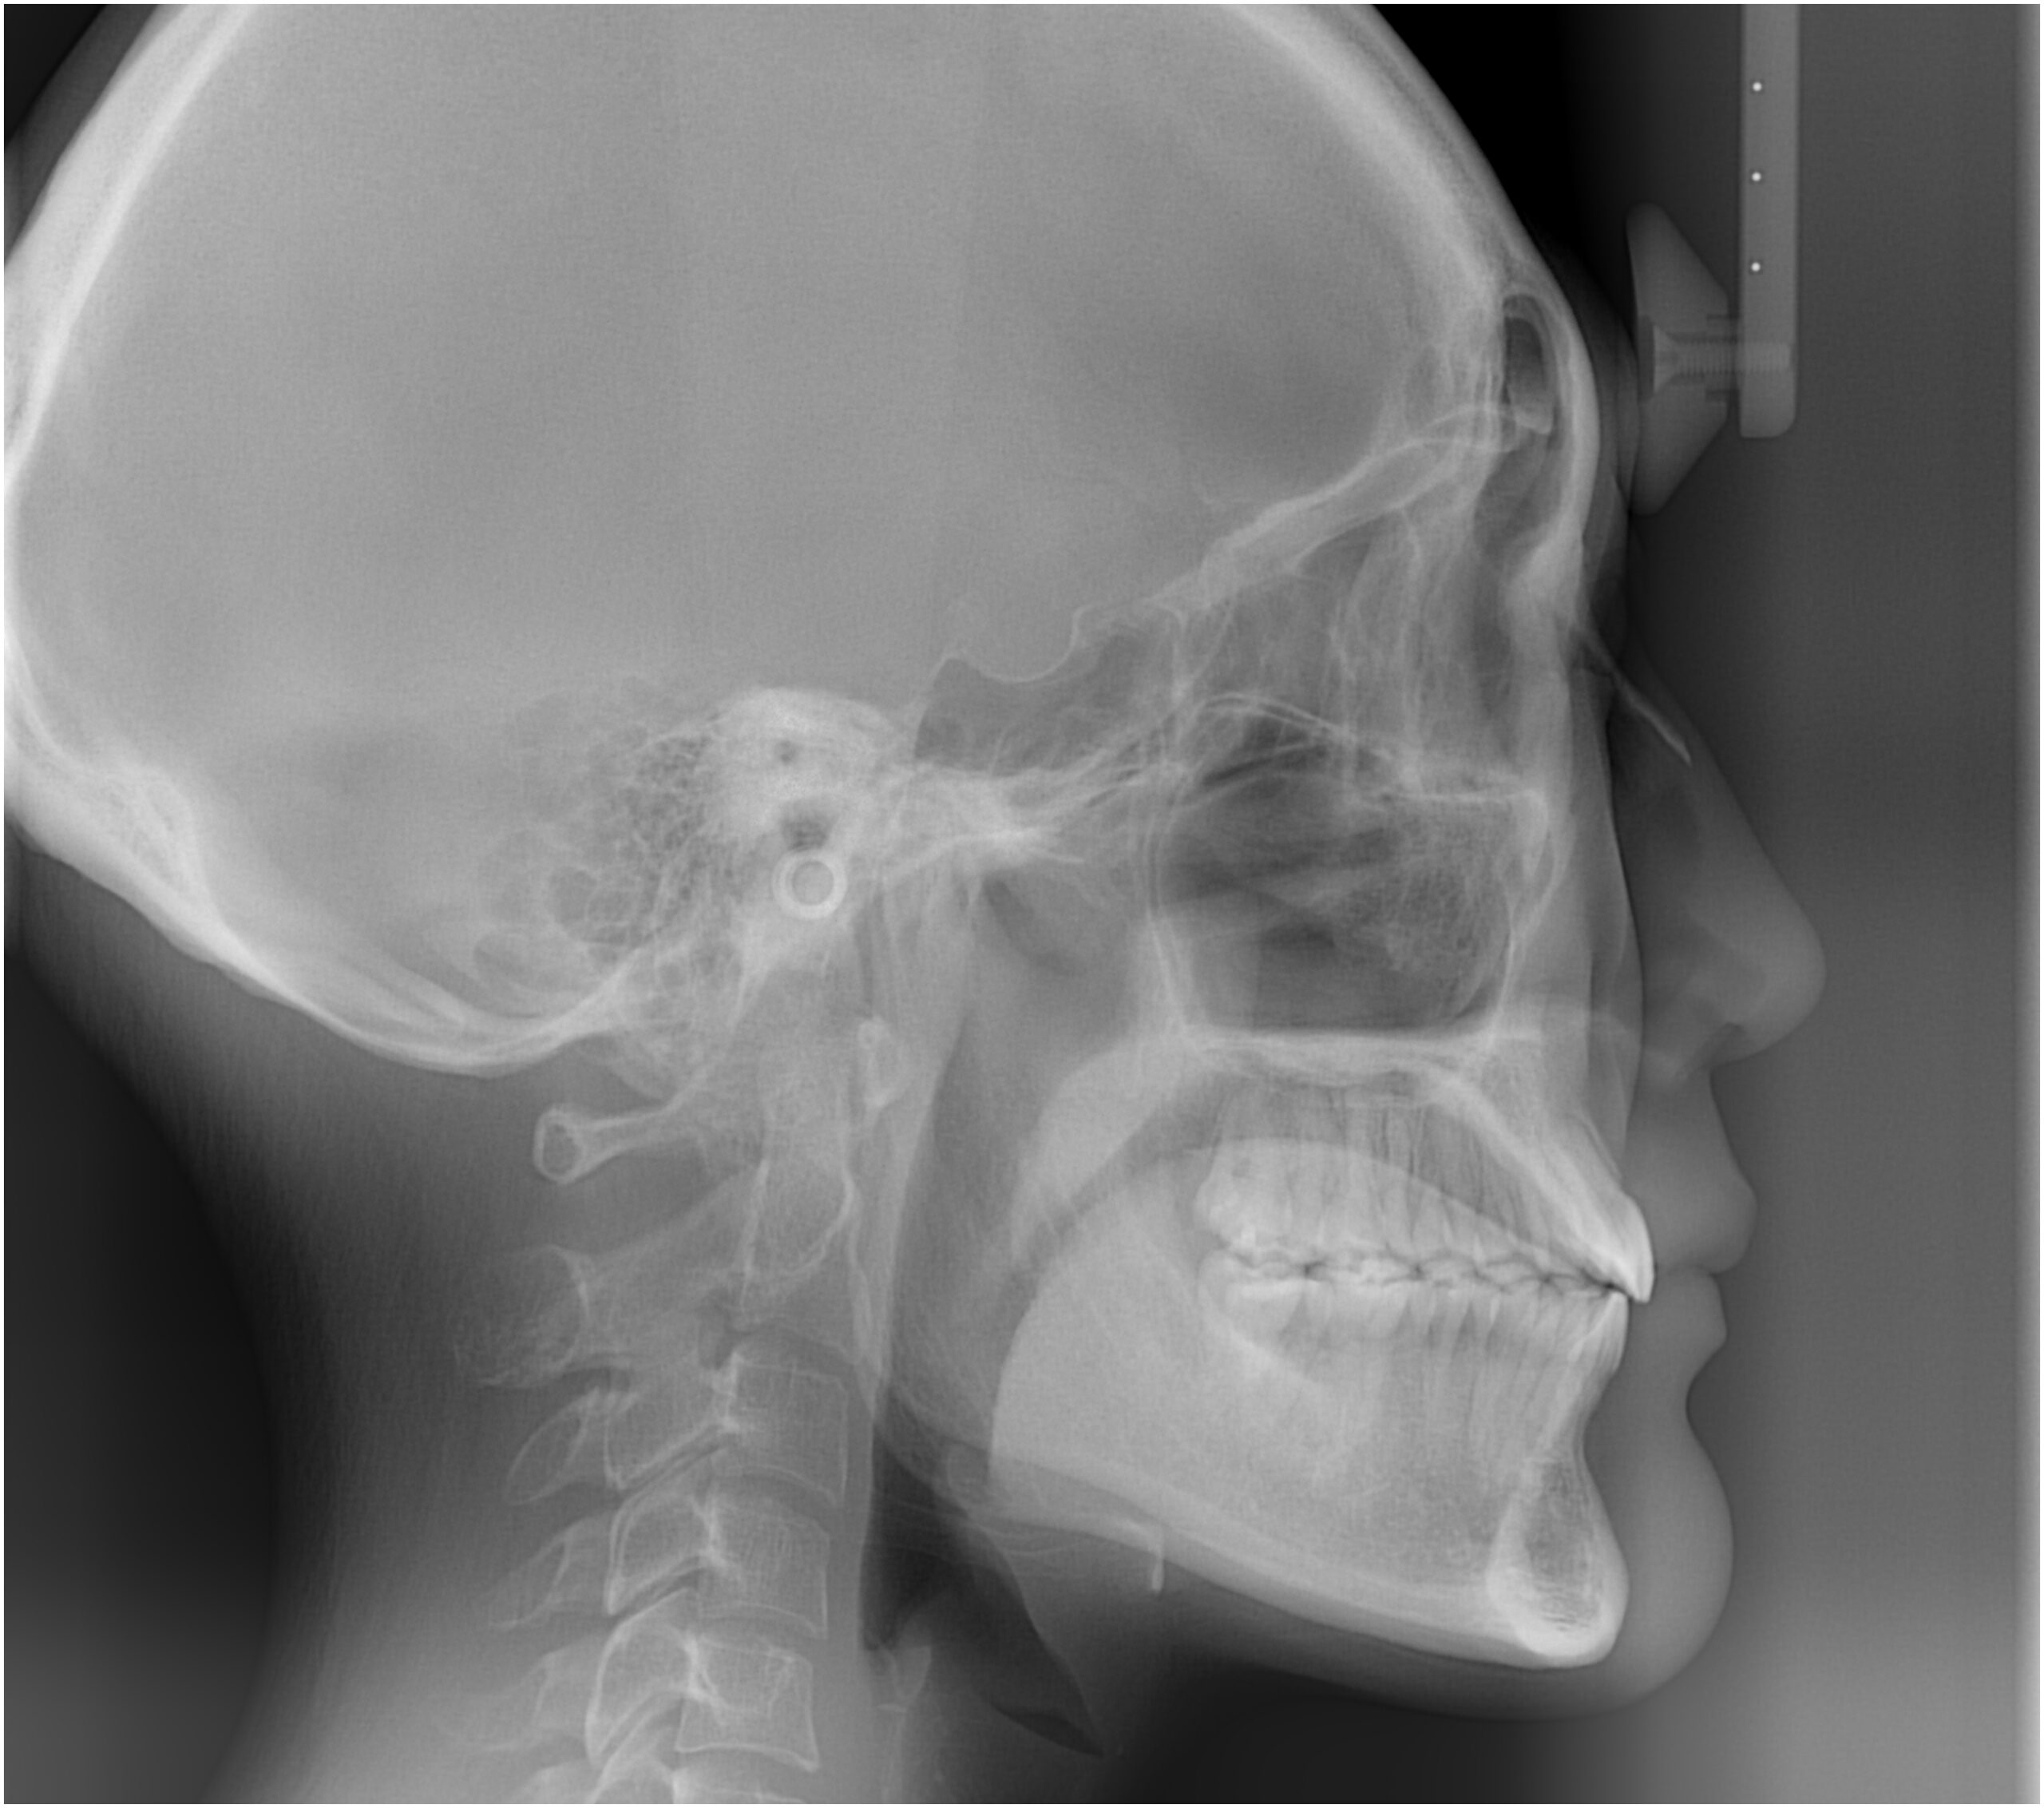

口腔内とラテラルセファログラムの変化

![]() | ![]() | ![]() |

| ↓ | ↓ | ↓ |

セファログラムのトレースの重ね合わせ(緑:治療前、赤:治療終了時)

| 治療後 | 前歯から奥歯まで全体的に緊密な咬み合わせになっています。 治療前後のセファログラムのトレースの重ね合わせを比較すると、上下の歯列の後方移動ができ、それにより口元もよりすっきりしました。 また前歯の唇側傾斜も改善されています。 |